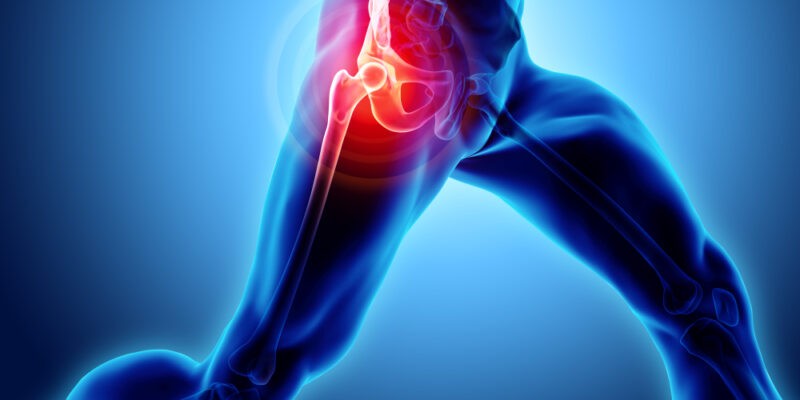

A 5ª Vara Cível de Cuiabá (MT) condenou o Bradesco Previdência e Seguros S/A e Mapfre Vida S/A, em 16 de novembro de 2022, a pagar em torno de R$ 32 mil referentes a indenização por invalidez permanente por acidentes a um militar que teve fraturas na bacia e no fêmur esquerdo em decorrência de um acidente de trânsito.

Prossegue que, após o ocorrido, seu cliente precisou de atendimento médico e foi submetido à cirurgia para fixação de acetábulo (local onde a cabeça do fêmur articula-se com a pelve). Porém, apesar de ter realizado todo o tratamento médico indicado, está incapacitado para a profissão militar do Exército Brasileiro.

“O laudo pericial concluiu que trata-se de uma invalidez permanente, parcial e incompleta, do membro inferior esquerdo, de média repercussão. De acordo com a tabela da Superintendência de Seguros Privados. (SUSEP), prevista em contrato, a valoração do dano corporal é de 35%. Em virtude da sequela do membro inferior esquerdo, restou incapacidade permanente para o trabalho na função de militar, a qual exercia anteriormente ao acidente. Entretanto, possui capacidade residual para exercer outra atividade, desta forma, foi readaptado para função administrativa”, explica o advogado.